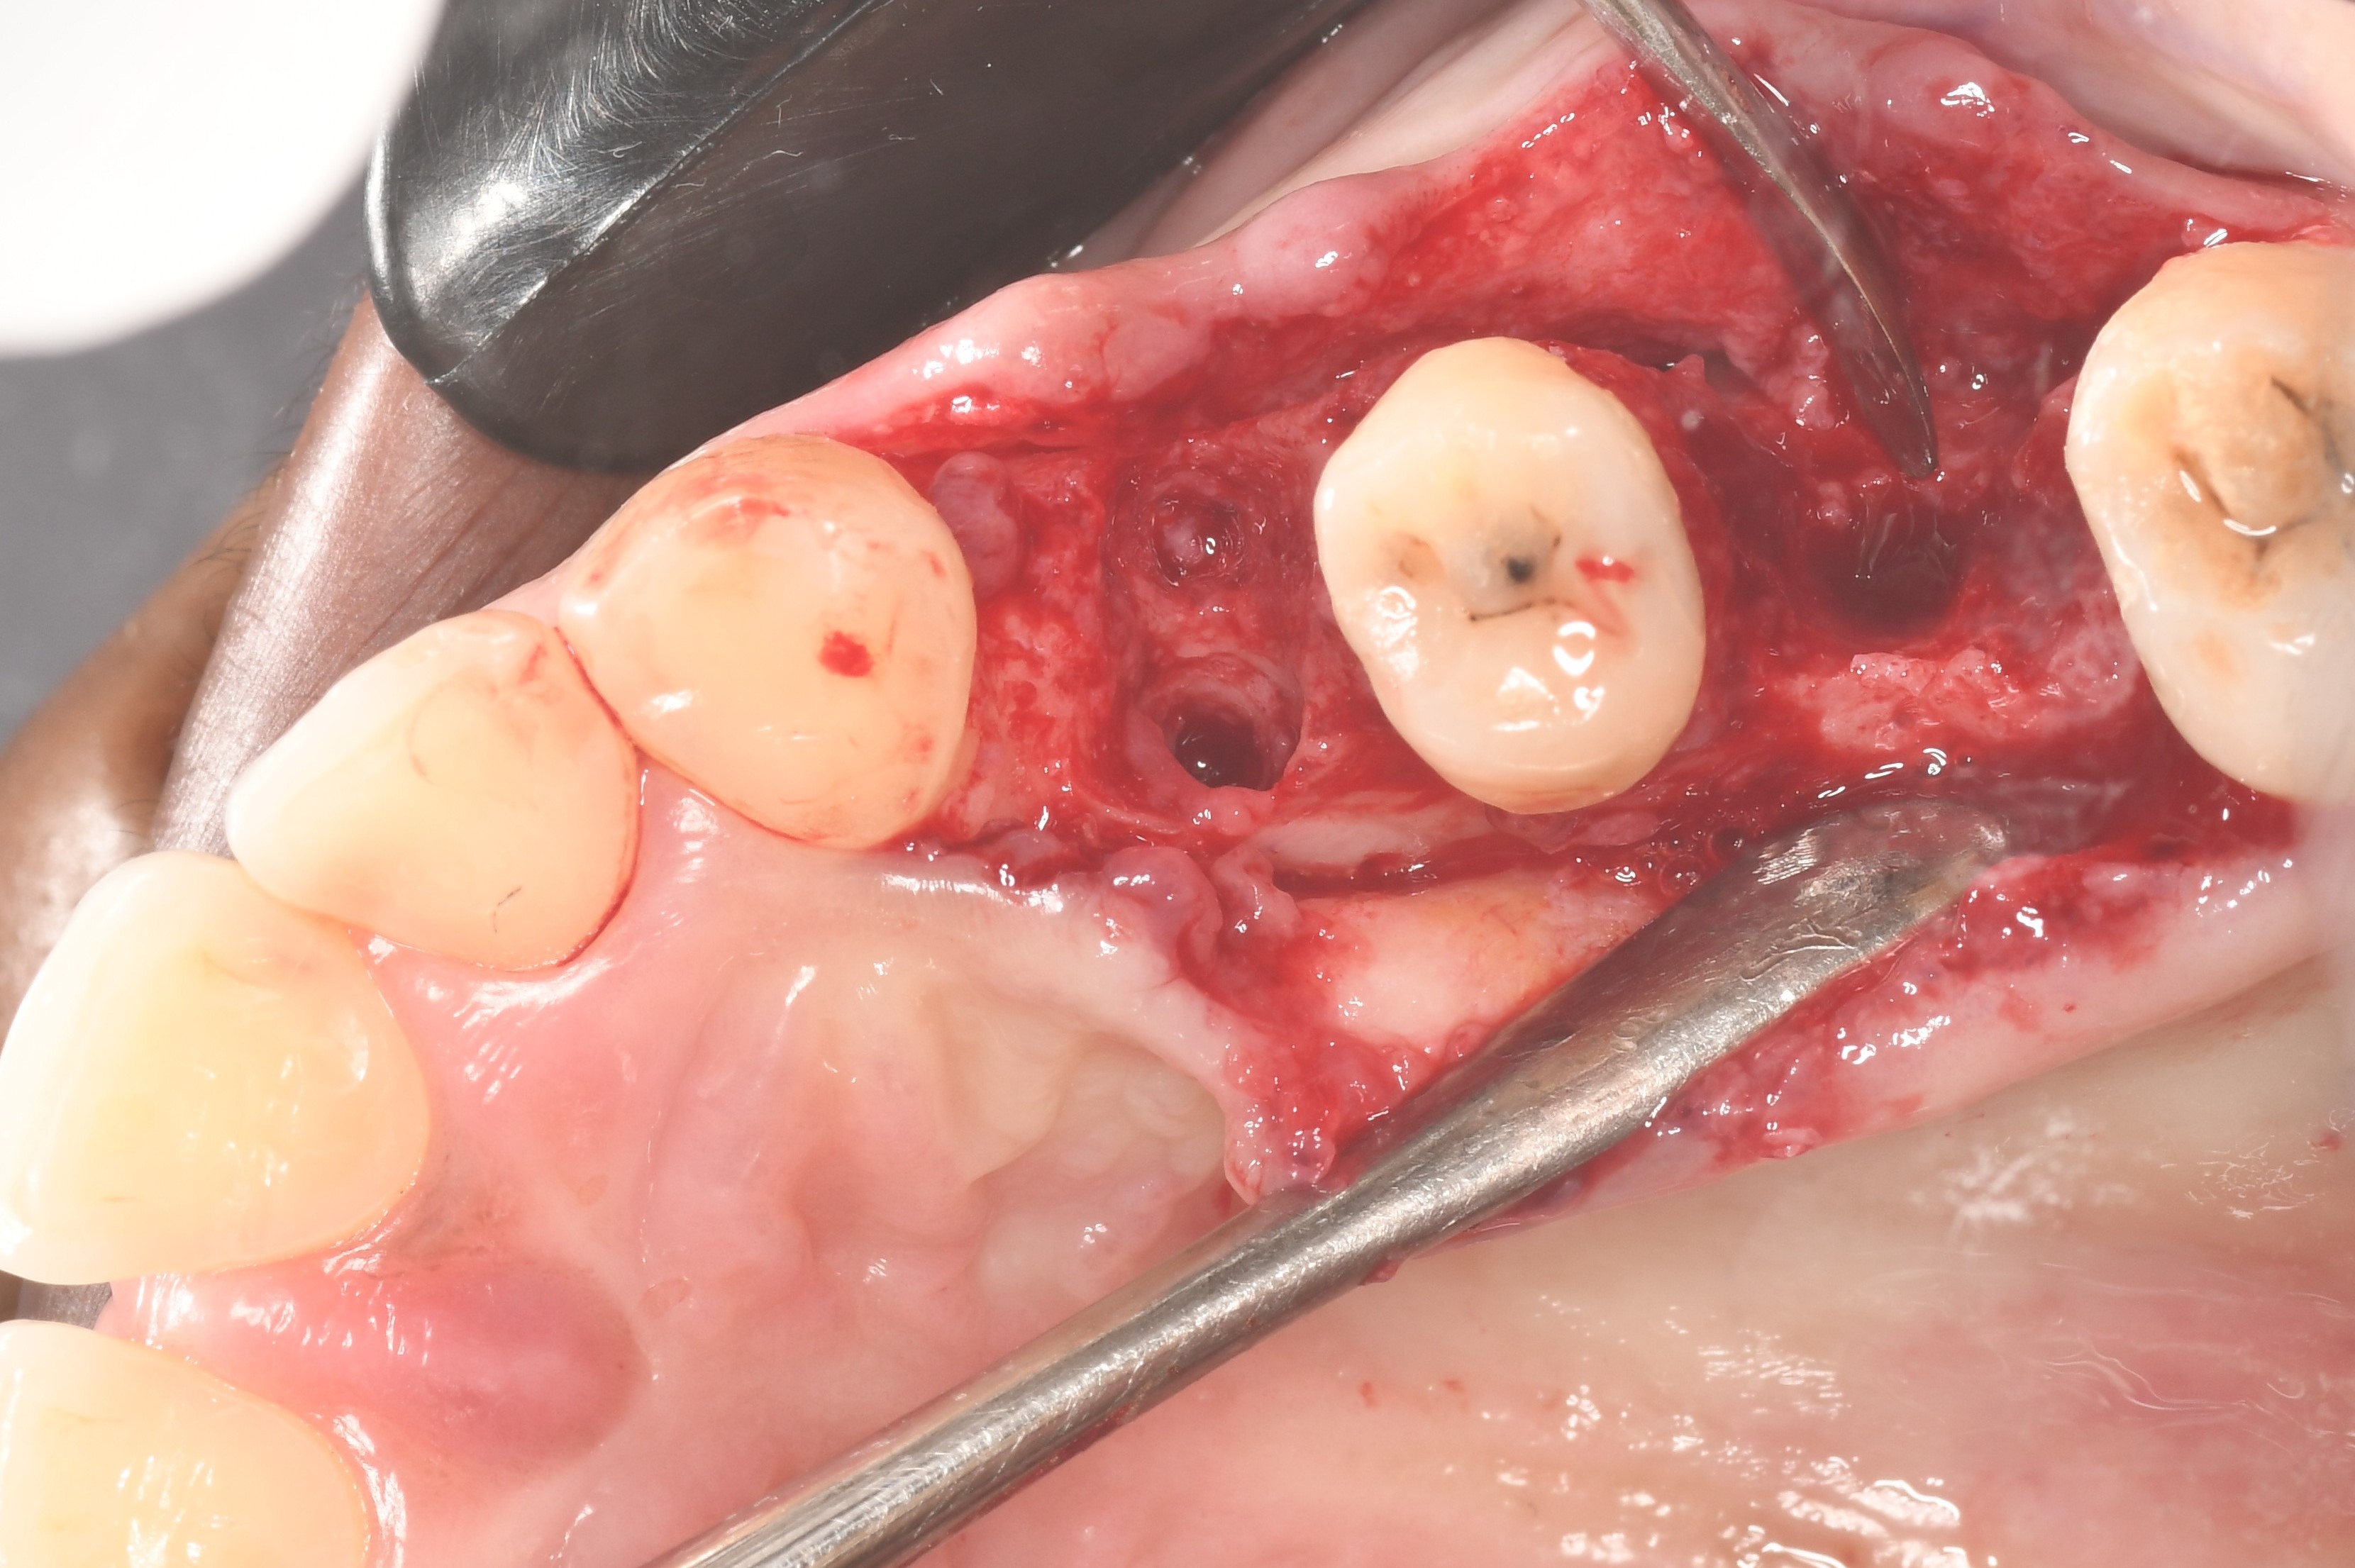

Surgical procedure:

Placement of a DSI Allograft bone graft covered with PRF and sutured with DSI Nylon 4/0 and covered with DSI Unilite Flow.